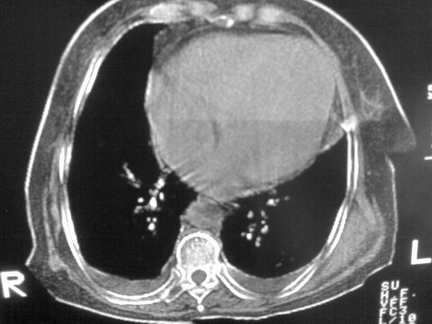

标题: CT13142:女 80 胸闷、气短、1w [打印本页]

标题: CT13142:女 80 胸闷、气短、1w

右肺炎性变,双侧甲状腺肿,胸膜肥厚。

右肺炎性变

双侧胸腔积液

缩窄性心包炎

左室为主的心脏增大。

胸膜肥厚,

气管,支气管软骨钙化。

右肺感染;双侧胸腔少量积液,心影增大,可能与心功不全有关;胸内甲状腺肿。

右肺炎性变,双侧甲状腺肿,胸膜肥厚,心影增大考虑心功能不全.

胸内甲状腺肿;右肺感染;双侧胸腔少量积液。

胸内甲状腺肿;右肺中叶感染;双侧胸腔少量积液;心影增大,考虑有心功能不全。